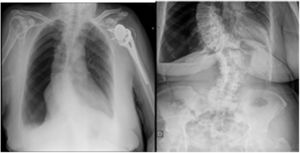

Mujer de 78 años con un índice de masa corporal (IMC) de 30,5 y antecedentes de colecistectomía a través de incisión subcostal derecha hace 42 años y hernioplastia umbilical hace cuatro años. Actualmente presenta eventración M2-3-4W2R1 (fig. 1) e índice de Tanaka de 28%, candidata a neumoperitoneo preoperatorio. Tras 72 horas de insuflación diaria de 1 litro, la paciente comienza con disnea y se realiza una radiografía abdomen-tórax, mostrando neumotórax masivo derecho (fig. 2) y requiriendo drenaje torácico e ingreso hospitalario. La paciente evoluciona favorablemente y es dada de alta al 6.° día.